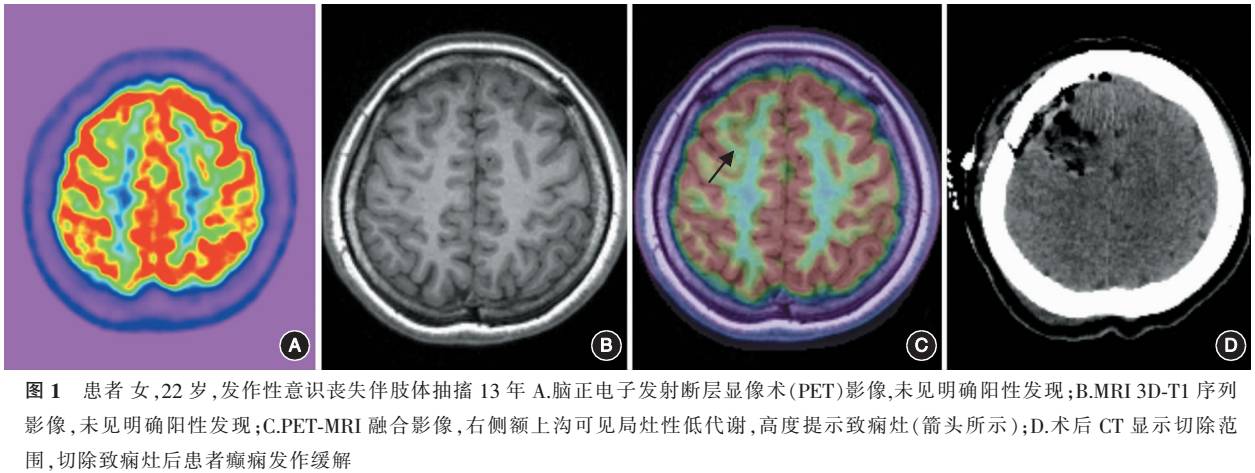

(3)影像后处理方法:将扫描得到的MRI 3D-T1序列影像以及PET影像(DICOM格式)导入基于MATLAB平台的SPM软件进行图形匹配,匹配好的MRI和PET影像使用Mricron进行影像叠加并添加伪彩形成PET-MRI融合影像(图1),随后对于低代谢区的识别由与上述检查相同的两名核医学科医师共同判读得出。

1. 病理学与随访结果:病理学结果显示,30例行手术切除致痫灶的患者中,局灶性脑皮质发育不良(focal cortical dysplasia,FCD)Ⅰ型3例,Ⅱ型12例,Ⅲa型[4]6例,海马硬化2例,7例病理学无法明确。术后平均随访12.5个月(4~20个月),其中Engel分级Ⅰ级23例(77%),Ⅱ级3例(10%),Ⅲ级3例(10%),Ⅳ级1例(3%)。4例未行手术切除的患者未纳入随访。